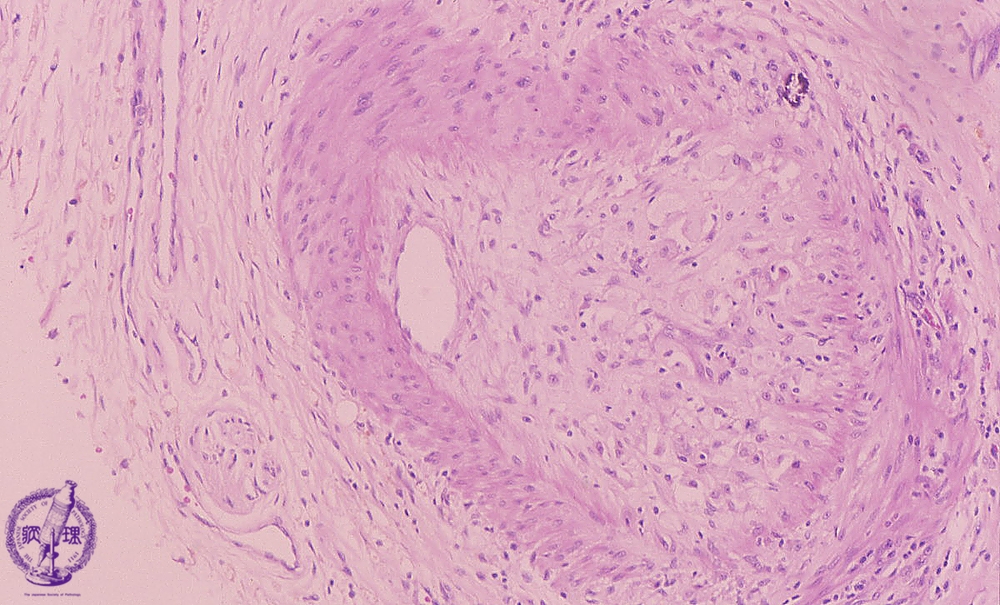

• 10.Liver

• (11)Transplantation rejection

Microscopic finding (HE stain, high power view): Foam cells infiltrate the portal hepatic artery intima and the latter undergoes fibrotic change with severe narrowing of the lumen.